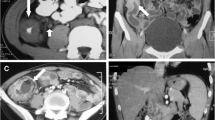

Eighty-two patients including 25 patients with ITB and 57 patients with CD were retrospectively recruited (54 in training cohort and 28 in testing cohort). The region of interest (ROI) for the lesion was delineated on magnetic resonance enterography (MRE) and colonoscopy images. Radiomic features were extracted by least absolute shrinkage and selection operator regression. Pathological feature was extracted automatically by deep-learning method. Clinical features were filtered by logistic regression analysis. Diagnostic performance was evaluated by receiver operating characteristic (ROC) curve and decision curve analysis (DCA). Delong’s test was applied to compare the efficiency between the multidisciplinary-based model and the other four single-disciplinary-based models.

The radiomics model based on MRE features yielded an AUC of 0.87 (95% confidence interval [CI] 0.68–0.96) on the test data set, which was similar to the clinical model (AUC, 0.90 [95% CI 0.71–0.98]) and higher than the colonoscopy radiomics model (AUC, 0.68 [95% CI 0.48–0.84]) and pathology deep-learning model (AUC, 0.70 [95% CI 0.49–0.85]). Multidisciplinary model, integrating 3 clinical, 21 MRE radiomic, 5 colonoscopy radiomic, and 4 pathology deep-learning features, could significantly improve the diagnostic performance (AUC of 0.94, 95% CI 0.78–1.00) on the bases of single-disciplinary-based models. DCA confirmed the clinical utility.

Multidisciplinary-based model integrating clinical, MRE, colonoscopy, and pathology features was useful in distinguishing ITB from CD.

Mao, R., W.D. Liao, Y. He, et al., Computed tomographic enterography adds value to colonoscopy in differentiating Crohn's disease from intestinal tuberculosis: a potential diagnostic algorithm. Endoscopy, 2015. 47(4): p. 322-9.

Zhao, X.S., Z.T. Wang, Z.Y. Wu, et al., Differentiation of Crohn's disease from intestinal tuberculosis by clinical and CT enterographic models. Inflamm Bowel Dis, 2014. 20(5): p. 916-25.